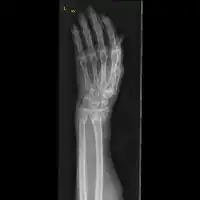

| Midshaft fracture of the radius and ulna | |

Front view of displaced fractured radius and ulna at wrist

Front view of bowing fractured radius and ulna